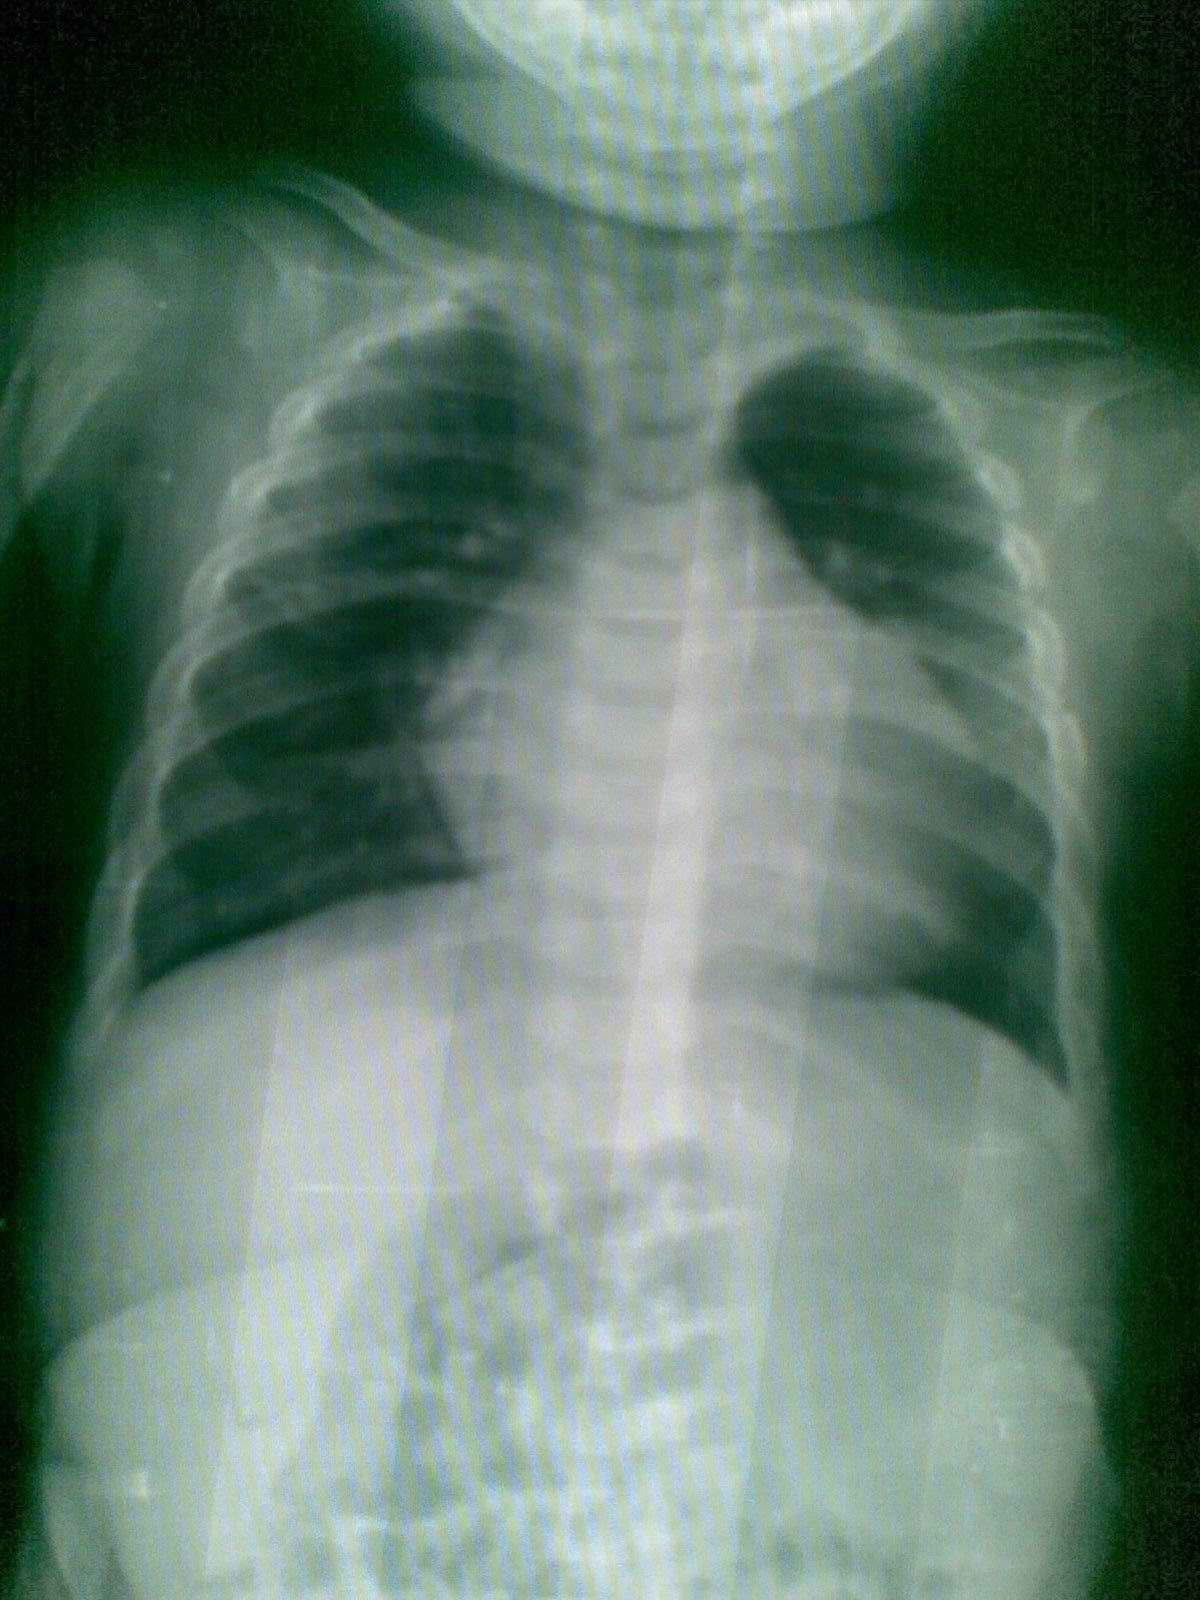

看这个小孩的心脏有问题吗?科里有医生说小孩的胸腺可以和心缘重叠,他说可能是胸腺,心脏没事,大家探讨下啊

他们说得对,小孩的胸腺可以和心缘重叠,可能是胸腺,心脏没事。

看小儿的心脏不能光以它的大小来衡量是否正常。

还要看肺门和肺血情况,并结合临床的其它检查。

这个小儿的肺血管纹理是正常的。

图像不是很清晰,不好说肺血正不正常。

睡着的心影大些,不能确定。

是胸腺影,正常胸片.